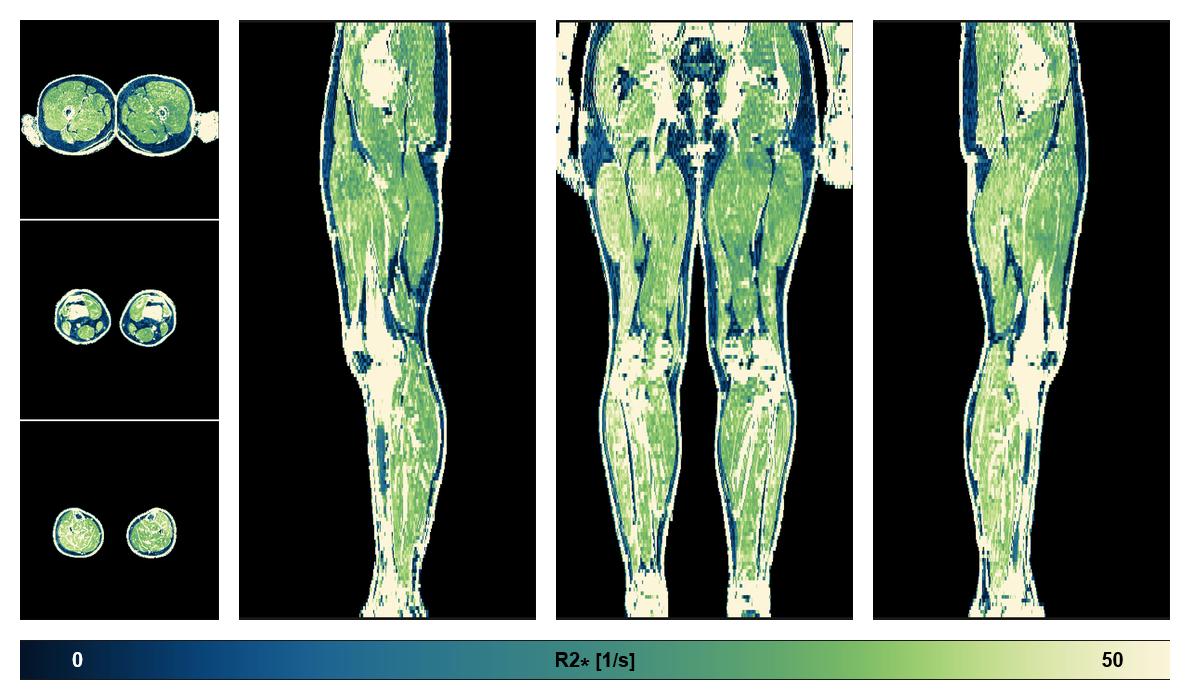

• R2 star relaxation

The R2 star relaxation time of the lower extremity obtained from the dixon reconstruction for muscle water fat quantification.